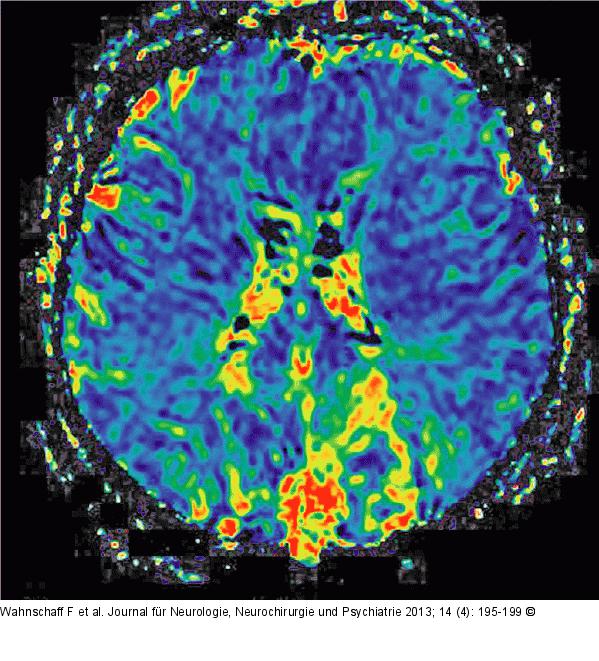

Abbildung 6: Hypophysenadenom Postoperative cMRT mit „Mean-transit-time“- (MTT-) Sequenz und der Darstellung der Perfusionsareale beider Arteriae cerebri mediae und der linken Arteria cerebri anterior. |

Postoperative cMRT mit „Mean-transit-time“- (MTT-) Sequenz und der Darstellung der Perfusionsareale beider Arteriae cerebri mediae und der linken Arteria cerebri anterior. |